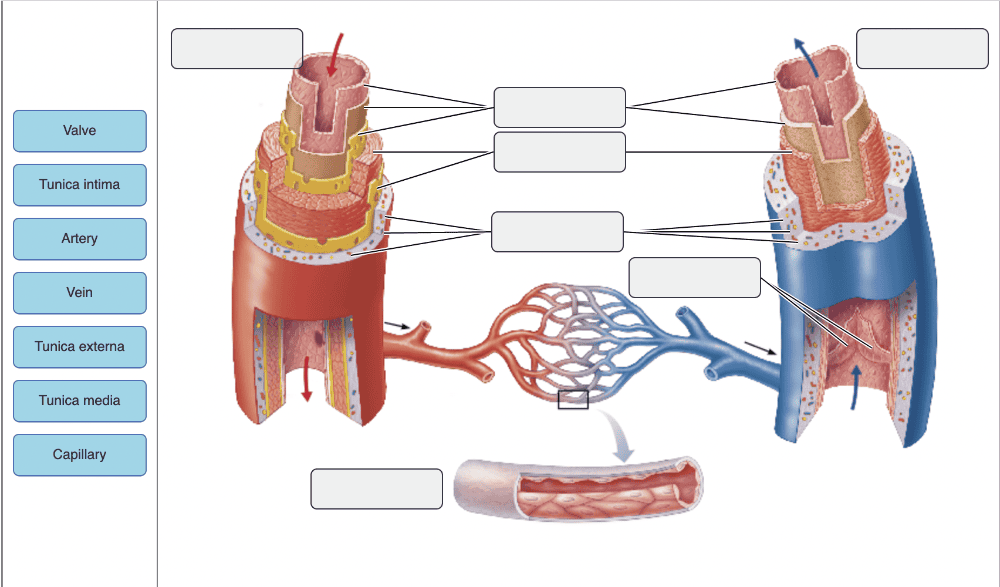

Drag the appropriate labels to their respective targets.

Drag the appropriate labels to their respective targets.